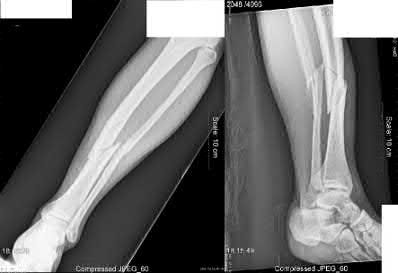

Figure B shows a midshaft tibia fracture with an intact fibula, which places the fracture at increased risk of varus malalignment during healing.

Nonsurgically treated tibial shaft fractures with an intact fibula have an increased risk of varus malunion when treated nonsurgically. The fibula acts as a strut, preventing valgus collapse, but predisposing to varus angulation. Limb-length discrepancies can also occur.